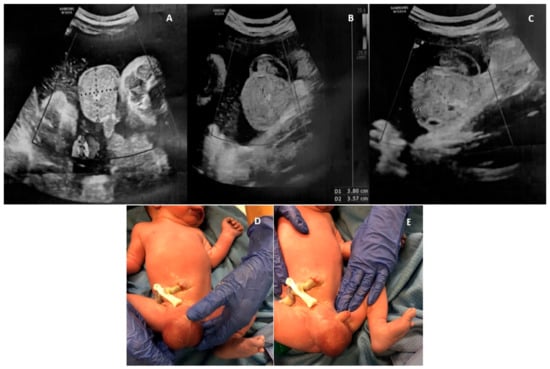

2. Case Report